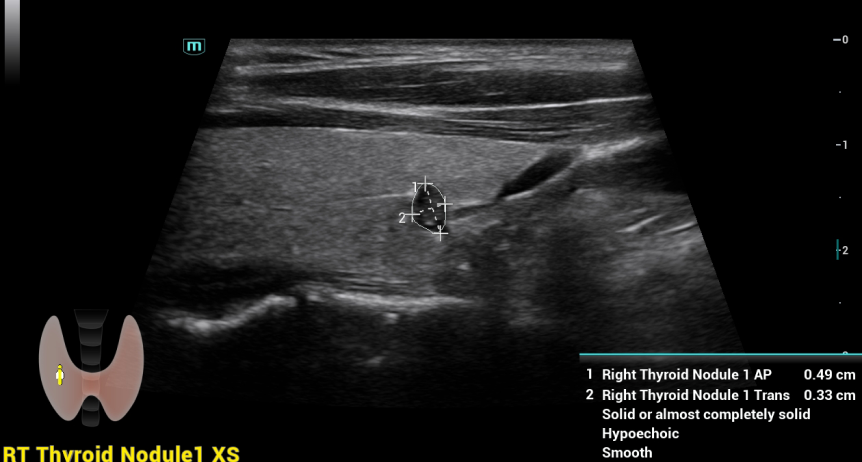

SMART THYROID